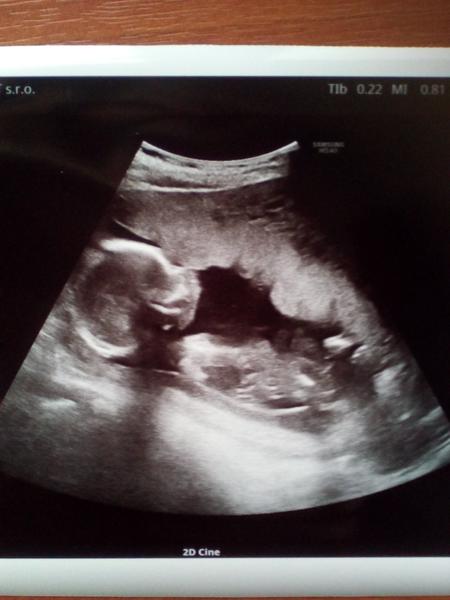

U nás novinky jsou,opatrně hladím že z hematomu zbývá už jen maličké cosi,konečně nespinim a snad už se ten zbytek jen vstřebá ,miminku se daří dle všeho dobře,jen doufám že nám to potvrdí ještě na screeningu po novém roce,ale včera jsem prcka viděla,na fotku to moc nebylo ale že je to chlap jak se patří nám ukázal pořádně,takže čekáme kluka 😂

@saminomimino ahoj. Vylustila jsem to. Ke klukovi gratuluju. Sice ja to na fotce nenasla. Uz mate vybrane jmeno?

@janadora na fote je jen miminko ne pindík 😀 Jméno máme jen pro holku 😀

@saminomimino fajn, že se to u vás zlepšilo 👍 takže takhle vypadá pindík na utz, jo? 😁 Já to nechci vědět a manžel ano 😂

@lazuli35 ne pindík tam není to je jen malej😂